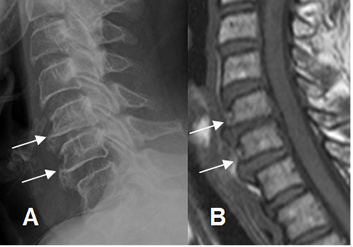

Fig 44. Cambios degenerativos.

A: Rx lateral y B: RM sagital en T1. Formación de osteofitos en la parte anterior de los cuerpos cervicales, por proceso degenerativo.